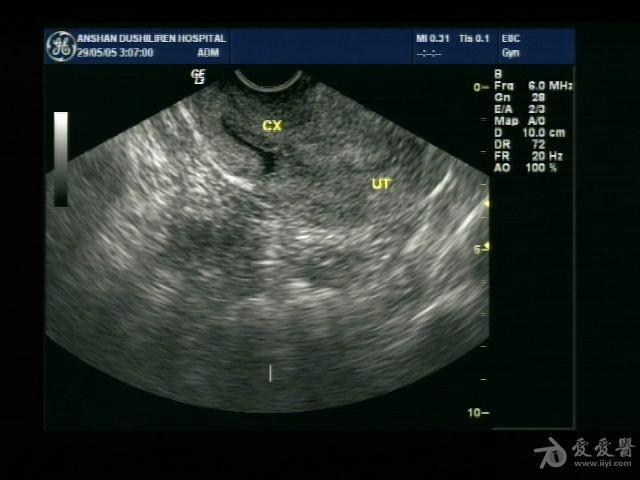

宫颈管积液,是什么原因呢